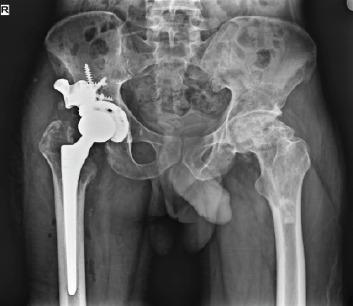

This retrospective case series includes seven patients who underwent revision THA for Paprosky grade 3 acetabular bone loss between January 2023 and April 2024 at two high-volume tertiary care centers. The mean age of the patients was 45 years, with three males and four females included in the study. Pre-operative planning involved advanced imaging techniques, including 3D-computed tomography scans and custom virtual modeling, to design the acetabular components tailored to each patient's specific anatomical requirements.During the surgeries, custom-made 3D-printed titanium augments and cages were used. These implants were fabricated using in-house software, and the turnaround time from the decision to surgery was approximately 10 days. Post-operatively, the planned 3D model was superimposed on post-operative radiographs to assess implant placement accuracy. The Harris hip score at the final follow-up averaged 69.16, with no signs of implant loosening observed.

本回顾性病例系列包括7例患者,他们于2023年1月至2024年4月在两家大型三级医疗中心接受了因Paprosky 3级髋臼骨丢失而进行的翻修全髋关节置换术。患者的平均年龄为45岁,研究纳入了3名男性和4名女性。术前规划涉及先进的成像技术,包括3D计算机断层扫描和定制虚拟建模,以设计适合每个患者特定解剖需求的髋臼组件。在手术过程中,使用了定制的3D打印钛增强物和笼。这些植入物使用内部软件制造,从决定手术到手术的周转时间约为10天。术后,将计划的3D模型叠加在术后X线片上以评估植入物放置的准确性。最后一次随访时的Harris髋关节评分平均为69.16,未观察到植入物松动的迹象。